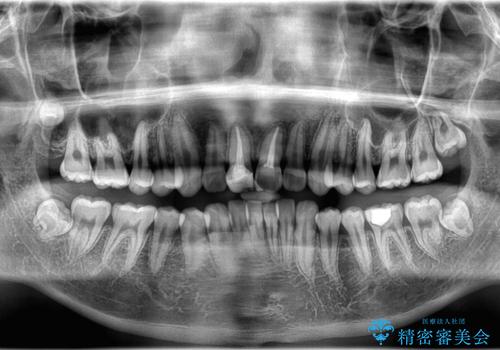

- 「歯のでこぼこを治したい 1年くらいで矯正を終わらせたい」を主訴に来院された患者様です。

叢生量は多く無く歯の傾斜も標準傾斜だったので歯は抜かずにワイヤー矯正で治療を行いました。

左側は2級傾向が強く臼歯の遠心移動をご提案しましたが、1年以内に矯正を終わらせたいという患者様のご意向で希望されず叢生を改善する矯正となりました。